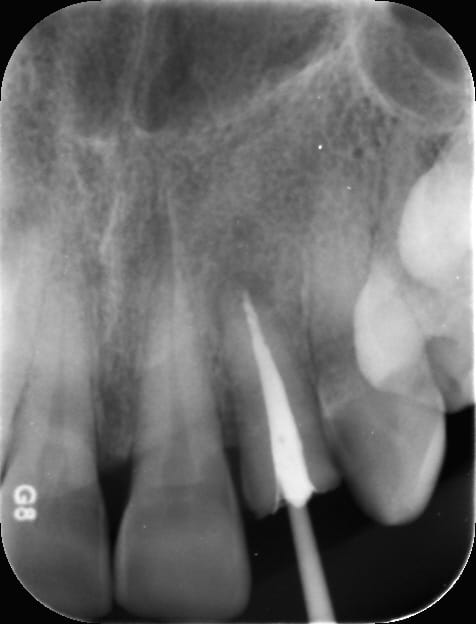

C'est la pulpe, c'est la pulpe !

Pulpe rétractée on va s'amuser à travers le bridge. -)

Capture d écran 2017 02 09 15.32 - Eugenol

Oh! C'est tout droit, tu nous as montré plus difficile.

Tout tout droit, une fois que tu es dedans oui :)

Avant d'être au chaud, il y a moyen de faire des bêtises :)

Capture d écran 2017 02 09 15.06 - Eugenol

il n'y a pas photo. Allez je te fais confiance, plein de RX pour valider ton axe et ton approche et tout va bien se passer. Avec un peu de chance tu flingueras le bridge et il sera à refaire ;-)

surtout que celle la il peut pas la tailler à ras

Piliers 34 et 38 faut oser. -)